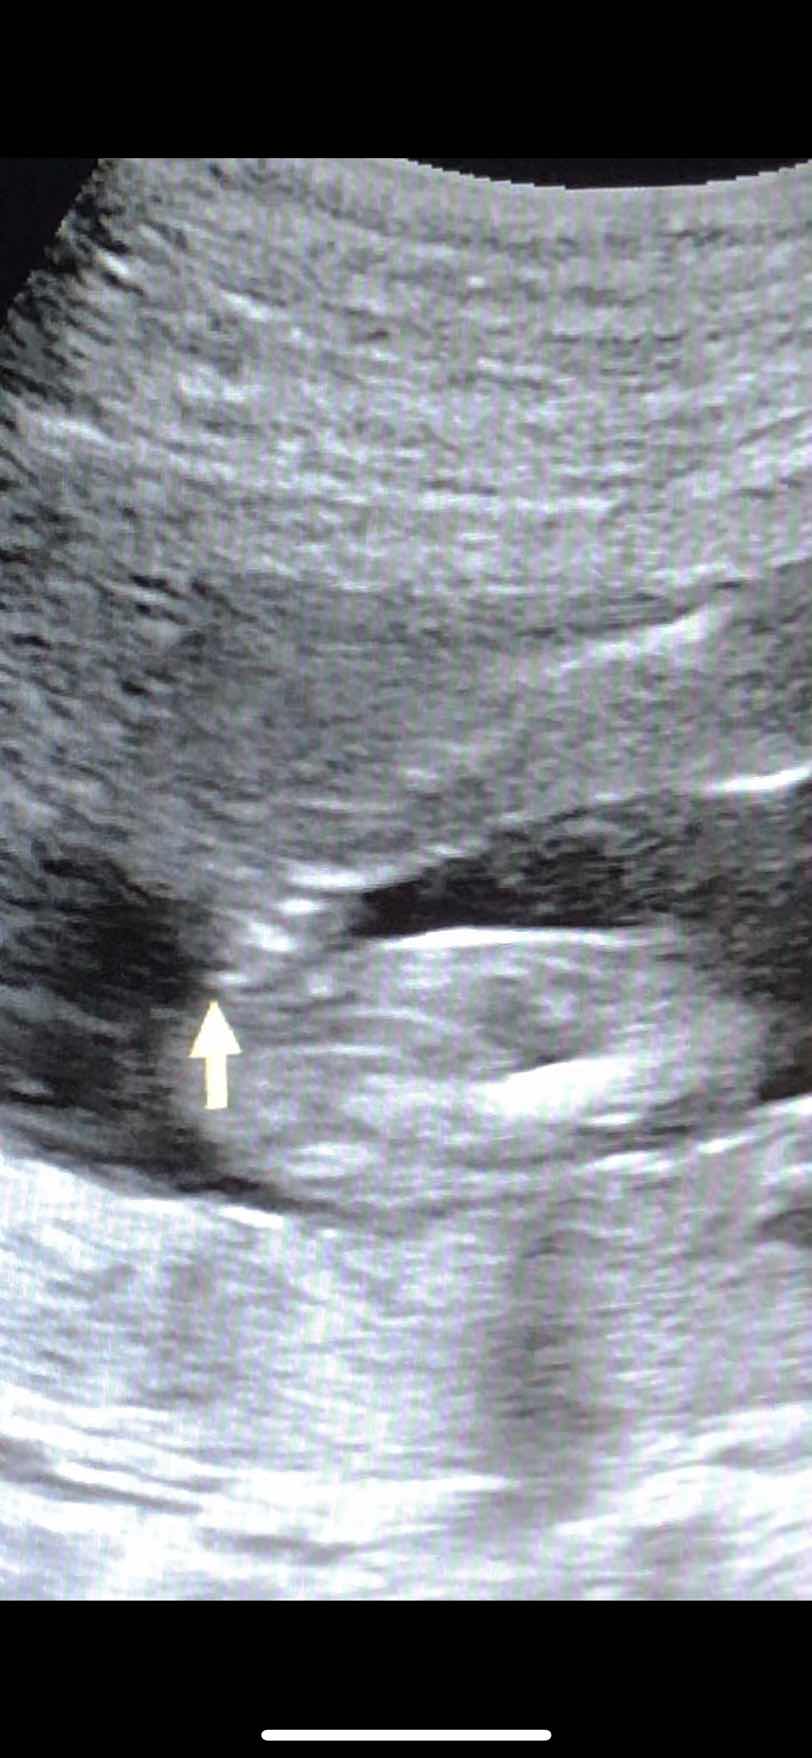

sure na po kayo yung gender ng baby ko. 5months nagpa ultrasound ako sabi girl. pwedi pa pobang magbago?

Kung malinaw pagkita ng nag ultrasound at kung maganda pwesto ni Baby baka sure na. Kadalasan kasing nagkakamali e yung hindi ayos pwesto ni baby.